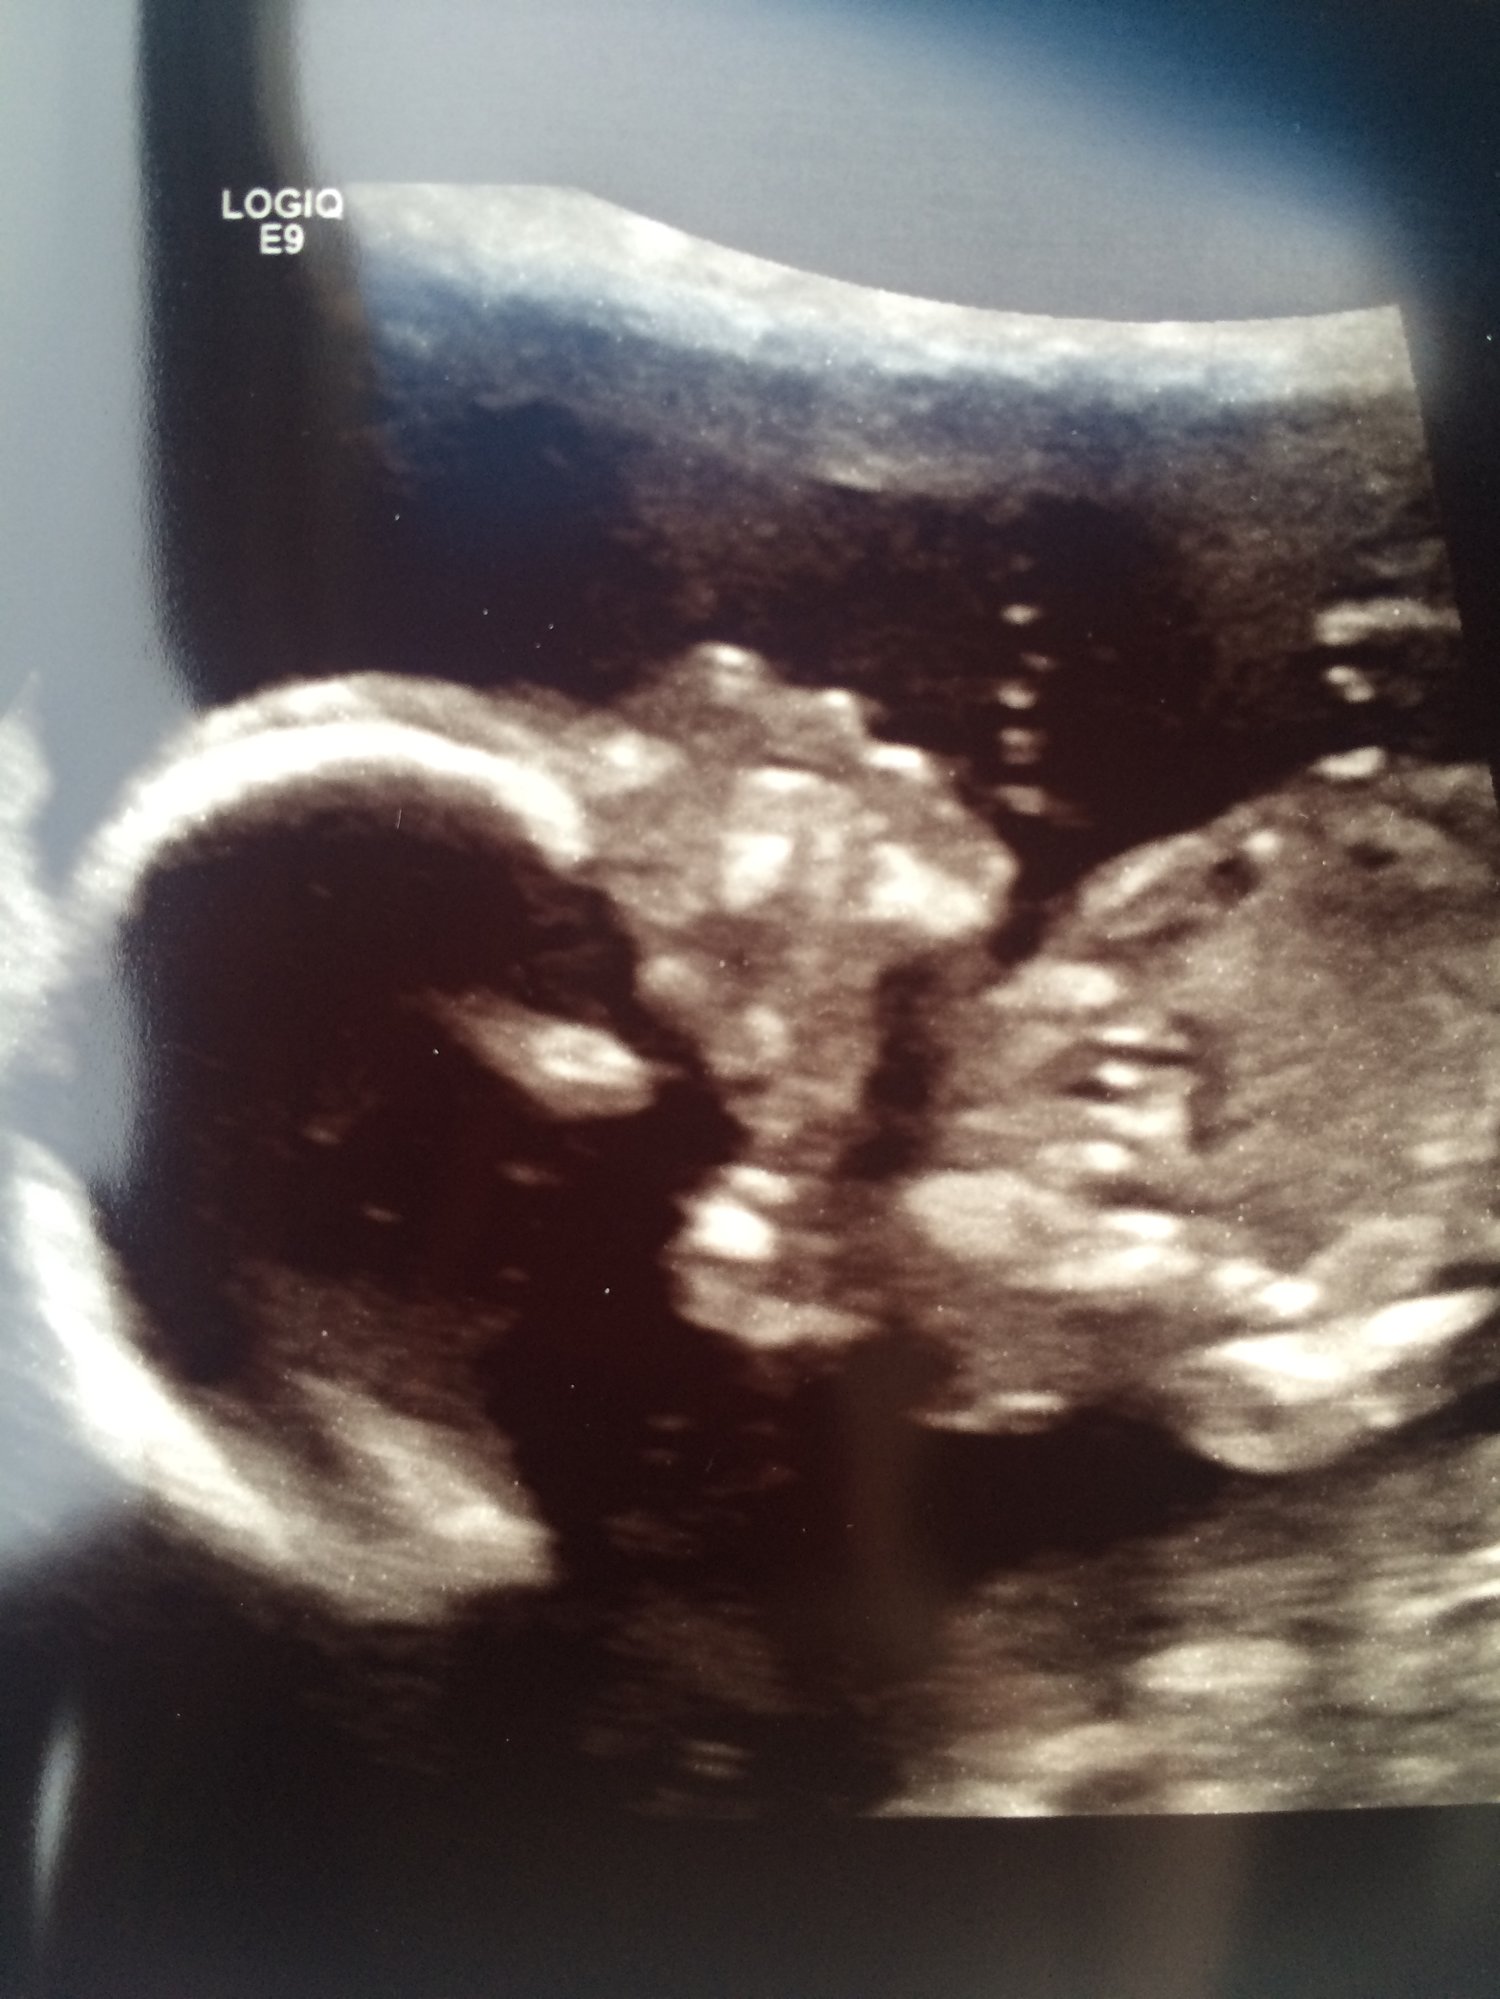

• @Hopeful_mom aww what a cutie!!! So glad it went well and you had a great tech :)

• @Hopeful_mom What an amazing picture! All of my anatomy scan pictures were not very clear. My baby just wasn't cooperating that day. I showed them to my parents and they were like ok. Didn't even know what we were looking for!

we also had our anatomy scan today too. He was swimming around everywhere and we confirmed it was a boy too. He wasn’t cooperating that much so I’m surprised she got a decent picture. Exciting for everyone getting theirs as we finally get to see the babies again after such a long break.

• @Hopeful_mom look at that little cutie pie! Love that. :)

• @holls214 awwww how cute - love it and I got a foot pic too soooo funny!  She showed me the baby pressing the foot down and i didn't feel it...so its interesting.  Did they tell you the size of the baby.  I believe mine is 13oz :)  I didn't get the inches next time ;)  @ReesaAnne16 and yes i think of all the IVF weight and i can't even let that get me down...from each cycle even from the IUIs i gained a couple of lbs and they all just added up...its worse now cause u just feel like a bigger marshmallow each day!!

@helloworld9 many of my pics were blurry I posted the best one, I"m thrilled!! We were spoiled with Vag US getting up close and personal with our beans as the belly sono looked like the babe shrunk at first.  At first my baby thought they were a lil cat all curled up and then luckily they started stretching :)

• such great u/s pics @Hopeful_mom@Holls214 :) and so glad everything came back clear!  I am having my anatomy scan on Monday and am starting to get nervous for it.  I hope I can just relax and enjoy it.

• Great pics @Holls214 !